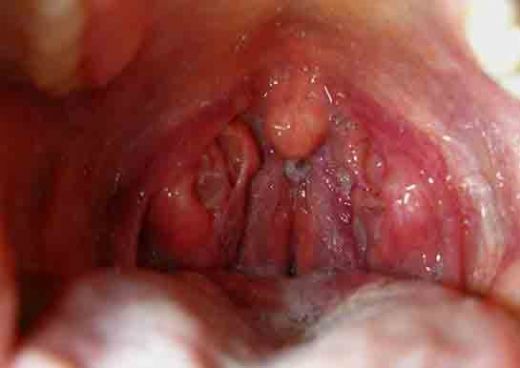

Bademcik İltihabı Nedir?Bademcik iltihabı, genellikle viral veya bakteriyel enfeksiyonlar sonucunda bademciklerin iltihaplanmasıdır. Bademcikler, boğazın arka tarafında bulunan ve vücudu enfeksiyonlara karşı koruyan lenfatik dokulardır. Bu durum, genellikle çocuklarda daha sık görülür, ancak her yaş grubunu etkileyebilir. Bademcik iltihabı, boğaz ağrısı, yutma zorluğu, ateş ve genel bir rahatsızlık hissi ile kendini gösterir. Bademcik İltihabının Belirtileri Bademcik iltihabının belirtileri genellikle şunlardır:

Bademcik İltihabı ve Belirtileri